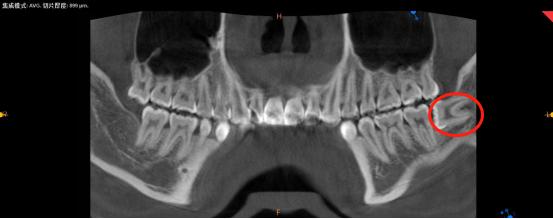

我们通常所讲的会造成严重后果的智齿,都是指下颌智齿。那么可能引起严重后果的下颌智齿又有哪些情况呢?如下图:

水平埋伏阻生

大家千万注意,长成以上类型的智齿都可能发炎,如果不对它们进行及时的处理,任由它发展下去的话,便会导致很严重的后果。所以对于上述所讲情况的智齿,都应该引起一定的重视,最好尽早将智齿拔除。

如果我们不把上图情况的智齿拔掉,最直接的影响就是智齿旁边的牙可能会被顶坏,导致牙髓发炎需要根管治疗,甚至牙根都可能烂掉,最终无法保留,只能拔除。